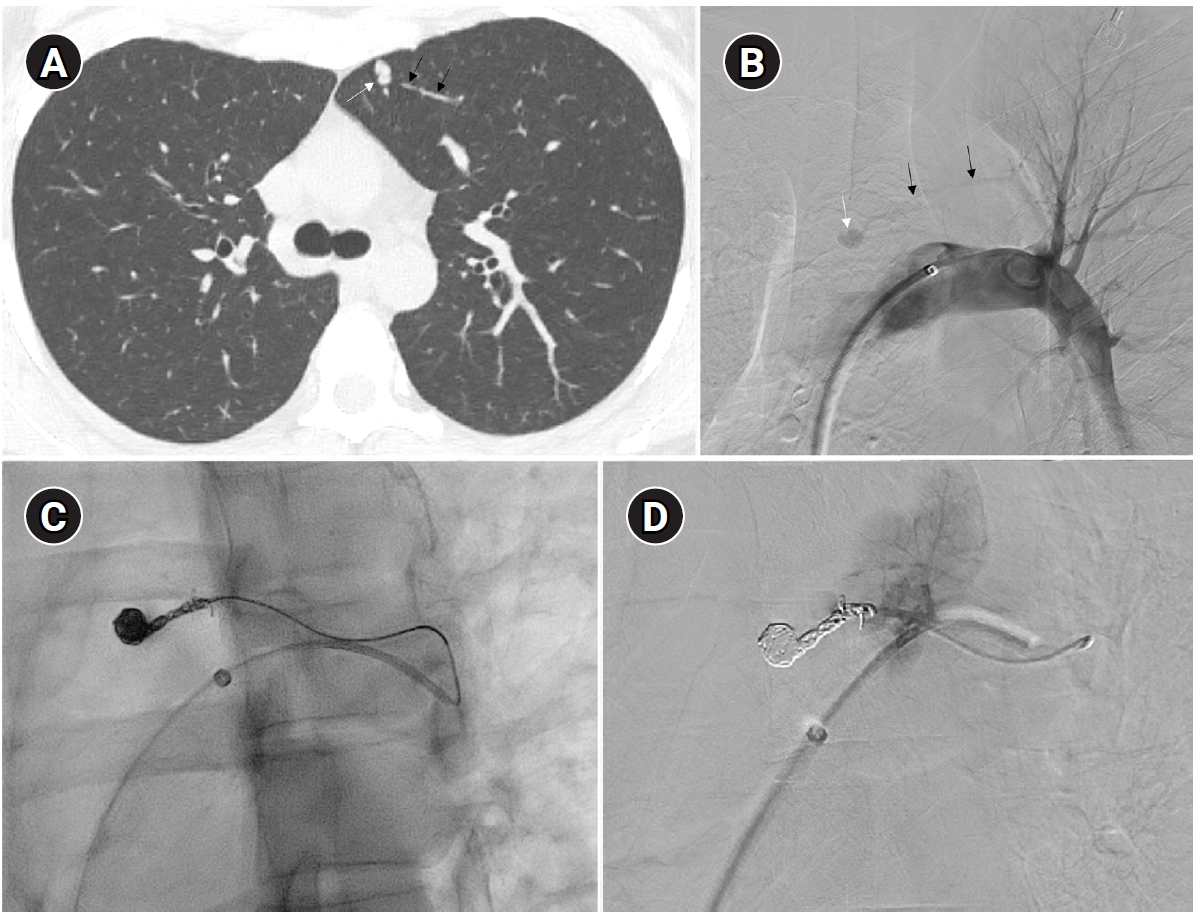

Embolization of a 1.5-mm feeding artery associated with an arteriovenous malformation in the left upper lobe of a 36-year-old female patient. (A) On the computed tomography (CT), a slender 1.5 mm feeding artery to the left upper lobe (black arrows) and a dilated venous sac (white arrow) are visible. (B) On angiography, the same finding as on the CT is observed (black arrows and white arrow), (C, D) A scene of coil embolization (C) and a post-embolization angiography image (D). In panel (D), the tri-axial system was utilized, including a 6-Fr Shuttle guiding catheter, a 5-Fr angled catheter, and a 1.9-Fr microcatheter, to access the feeding artery. Coil embolization was performed using Concerto 3D and Helix coils.

Fig. 2. Embolization of a 1.5-mm feeding artery associated with an arteriovenous malformation in the left upper lobe of a 36-year-old female patient. (A) On the computed tomography (CT), a slender 1.5 mm feeding artery to the left upper lobe (black arrows) and a dilated venous sac (white arrow) are visible. (B) On angiography, the same finding as on the CT is observed (black arrows and white arrow), (C, D) A scene of coil embolization (C) and a post-embolization angiography image (D). In panel (D), the tri-axial system was utilized, including a 6-Fr Shuttle guiding catheter, a 5-Fr angled catheter, and a 1.9-Fr microcatheter, to access the feeding artery. Coil embolization was performed using Concerto 3D and Helix coils.

To prevent paradoxical embolism or life-threatening bleeding, all detected PAVMs should be treated in adult patients. Historically, a feeding artery diameter of ‘3 mm’ was considered the minimal diameter criterion for treatment of PAVMs [2]. However, with advances in embolic devices and catheter systems, less than 3 mm feeding arteries ≥2 mm can now be embolized (Fig. 2) [11]. Pregnancy is a special risk factor in patients with PAVM, especially in the second and third trimesters due to a decrease in peripheral vascular resistance and an increase in cardiac output by nearly 50% [12]. A recent study in 244 pregnant women with HHT showed major complications in 13%, all in patients who had not been screened or treated for PAVMs prior to pregnancy [13]. Thus, all women with HHT considering pregnancy should be screened for PAVM with computed tomography (CT) and eventually treated prior to conception.

Historically, detachable balloons were used as an embolization material; however, they are no longer utilized in current practice [18]. In the context of PAVM embolization, the use of coils, vascular plugs, or a combination of both is now standard practice [19-21]. Since the development of detachable coils, they have offered advantages over pushable coils, particularly in terms of repositioning during the procedure. They can even be fully retrieved and redeployed if necessary, enhancing procedural safety and control. It is crucial to prioritize minimizing the recanalization rate while ensuring the overall safety of the procedure when selecting the appropriate embolic materials and techniques. Feeding artery coil embolization was historically regarded as the standard approach, whereas venous sac embolization was discouraged because of the perceived risk of rupture [22]. However, with the introduction of newer venous sac embolization techniques, recent findings now indicate that tightly packing the venous sac with coils can achieve a higher success rate than the traditional feeding artery approach (Fig. 2) [22-25]. Additionally, vascular plugs, including micro-vascular plugs (Medtronic, Minneapolis, MN, USA) and Amplatzer vascular plugs (Abbott Vascular, Saint Paul, MN, USA) have also demonstrated a higher success rate compared to feeding artery coil embolization (Fig. 4) [26-28]. In the case of vascular plugs, the risk of device migration is relatively low. Moreover, an additional advantage is that the device can be repositioned if the sizing is not ideal or if it is not deployed in the exact desired location. This flexibility enhances the precision of the procedure (Fig. 5). In a recent European guideline, there is also a recommendation to consider vascular plug embolization as a first-line option whenever possible, rather than coil embolization [11]. Additionally, a recent meta-analysis recommended vascular plugs or venous sac coil embolization, noting that vascular plugs had a recanalization rate of 13.6% compared to 32.7% for coil-only embolization. Similarly, venous sac embolization showed a 3.8% recanalization rate, while feeding artery embolization had a rate of 24.3%. Additionally, a recent meta-analysis has recommended the use of vascular plug or venous sac coil embolization, as these techniques have demonstrated a lower persistence rate compared to other methods [21]. This shift is largely in response to the relatively high recanalization rate associated with feeding coil embolization. In the case of embolization using vascular plugs, the plug should be deployed at the most distal segment of the feeding artery just before the venous sac in order to preserve the normal pulmonary artery. Since the pulmonary artery contains less elastin and has a thinner wall compared to systemic arteries, it is more distensible [29]. Therefore, in the author's experience, oversizing by about 50% to 100% has been effective in reducing the recanalization rate. When performing venous sac coil embolization, it is important to use coils large enough to create a stable framing coil larger than the draining vein diameter, thereby preventing coil migration. After establishing this frame, the venous sac and the proximal feeding artery should be carefully packed to achieve complete occlusion.